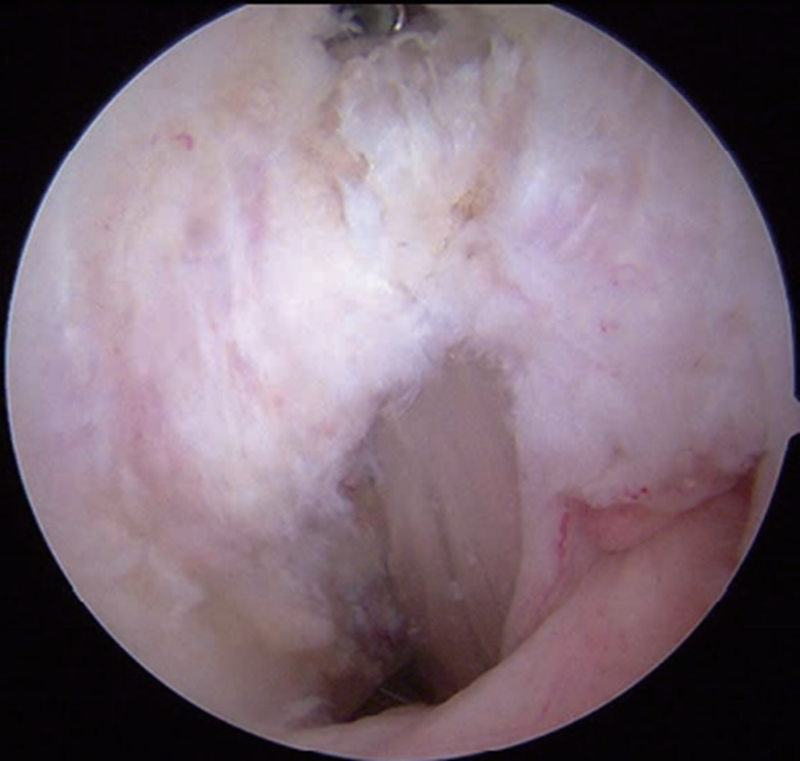

胫骨隧道外口放置在胫骨嵴偏外侧(图10),能更好地减少PCL移植物转折角以及在胫骨隧道内口的接触应力,降低韧带磨损或过度负荷。以后内侧入路为观察通道,从后外侧入路插入关节镜通道鞘管以保护后方血管、神经。直视下打入导针后,用移植物同号直径空心钻制备胫骨隧道。预置牵引线,并将关节镜通道鞘管置入牵引线前方以备协助牵拉移植物经过隧道。牵引线穿过胫骨和股骨隧道,在后方关节镜鞘的辅助牵引下将移植物引至合适位置。先固定股骨侧,固定胫骨侧前应将膝关节置于0°~30°屈伸范围,向前托起胫骨,避免其后坠,用9.1kg(20lb)的力量拉紧移植物并将其固定于胫骨侧(图11)。

图11 重建后的PCL

股骨止点周围组织是保留的原PCL残端